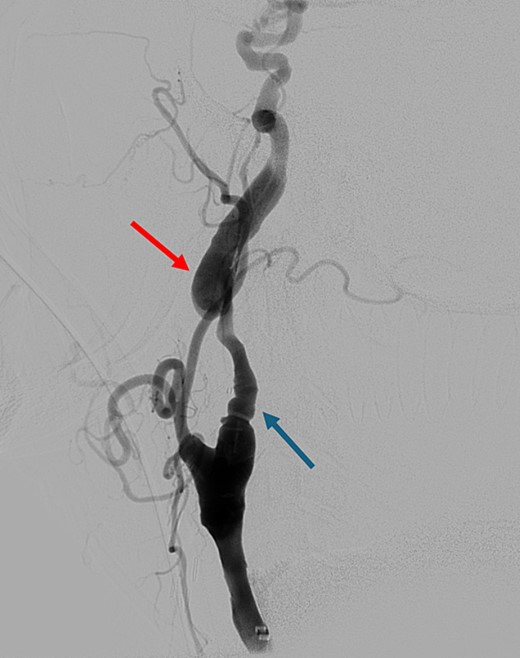

On presentation to the hospital, he was found to be in hypertensive crisis. Non-contrast head CT scan showed moderate volume biconvexity SAH (Fig. 1). CT angiography (CTA) of his head and neck showed a left internal carotid artery (ICA) dissection extending from the mid cervical segment to the level of the vertical petrous segment. Six vessel digital subtraction angiography confirmed a left ICA dissection extending from the proximal mid cervical ICA into the petrous segment. In the same region, there was also a left pseudoaneurysm formation with slight turbulent flow and stagnation (Fig. 2).

Digital subtraction angiography showing left internal carotid artery dissection (arrow on the left) with pseudoaneurysm formation (arrow on the right).